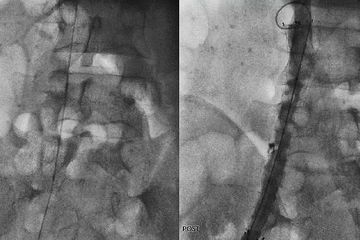

علاج ضيق الاوعية الدموية الطرفية, علاج انسداد الاوعيه ...

علاج ضيق الاوعية الدموية الطرفية, علاج انسداد الاوعيه ... from del-pa.pw